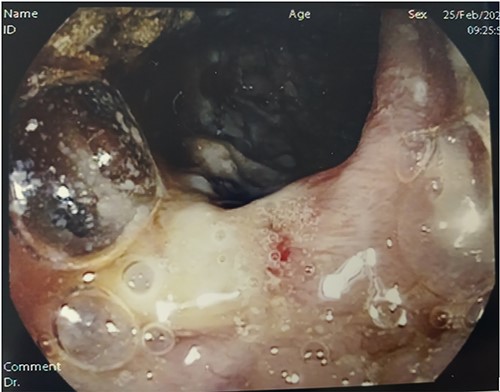

The following tests were carried out in ER: swab for severe acute respiratory syndrome coronavirus 2 (SARS-CoV2; negative), electrocardiogram, blood tests showing normocytic anemia, without leukocytosis, mild lymphocytopenia, and elevated C-reactive protein (CRP, 47 mg/L), chest X-ray (negative). Contrast-enhanced computed tomography (CT) showed increased densification of adipose tissue along the whole colon, the cecum and part of the ascendant had thickened walls (Fig. 1, panel A and B) with enhancement of the mucosa and submucosa edema, locoregional lymphoglandular large ~2 cm also partially colliquate (Fig. 1, panel C and D); lumen narrowing and strictures along the preterminal ileum and ascites. A colonscopy was performed, which revealed a patulous ileocecal valve, a bowel that was completely subverted from the cecum to the hepatic flexure with multiple and extensive deep fibrin-coated ulcers; the residual mucosa appeared pink with multiple pseudopolipoid protrusions (Fig. 2). Tests for HIV, HCV, stool cultures, parasitological and Clostridium difficile toxin were all negative and she was immune to hepatitis B virus. Quantiferon-test still outstanding.

Colonoscopy. Digital photograph from optical colonoscopy shows the endoscopic capture of suffering and ischemic mucosa with deep fibrin-coated ulcers.